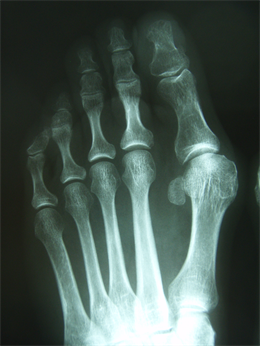

Figure 4. Patient Nr. 1: Recurrance of preoperated hallux valgus and hammertoe II.

Figure 5. Patient Nr. 1. Correction of a pathological DMAA without loss of length. Distal fragment has only a point contact to the proximal bone partner. Additional Akin osteotomy and PIP arthrodesis and FDL tranfer on the 2nd toe.